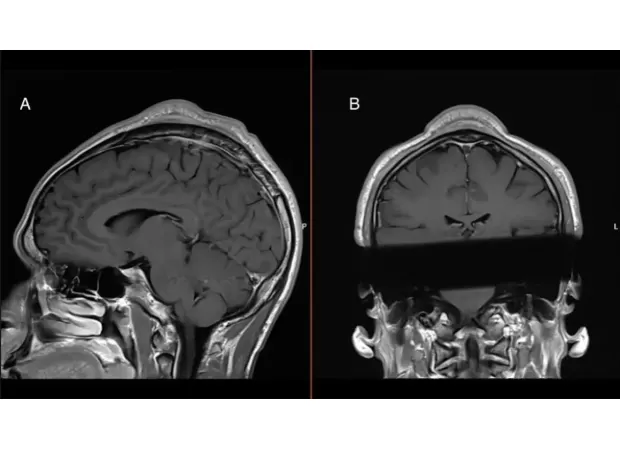

Some of the common injuries associated with breaking include carpal tunnel syndrome and other nerve problems. However, the case report highlights a lesser-known condition known as "headspin hole." This overuse injury is characterized by hair loss, which can eventually lead to a significant bump on the top of the head. The report, published in the medical journal BMJ, features a man in his early 30s who had been breakdancing for almost two decades and was diagnosed with a benign tumor that measured over 30cm in length and 2.5cm in thickness.

According to Dr. Christian Baastrup Søndergaard, a neurosurgery specialist at Rigshospitalet in Copenhagen and co-author of the case report, the condition is likely caused by repeated friction between the scalp and the floor during headspins. This, combined with the weight-bearing nature of the move, can lead to inflammation and minor bleeding, eventually resulting in scar tissue and the characteristic bulge on the scalp.